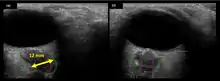

The astronauts affected by long term visual changes and prolonged intracranial hypertension have all been male, and SOS may explain this because in men, the sternocleidomastoid muscle is typically thicker than in women and may contribute to more compression. The reason that SOS does not occur in all individuals may be related to anatomic variations in the internal jugular vein. Ultrasound study has shown that in some individuals, the internal jugular vein is located in a more lateral position to Zone I compression, and therefore not as much compression will occur, allowing continued blood flow.

In 1G on earth, the main outflow of blood from the head is due to gravity, rather than a pumping or vacuum mechanism. In a standing position, the main outflow from the head is through the vertebral venous system because the internal jugular veins, located primarily between the carotid artery and the sternocleidomastoid muscle are partially or completely occluded due to the pressure from these structures, and in a supine position, the main outflow is through the internal jugular veins as they have fallen laterally due to the weight of the contained blood, are no longer compressed and have greatly expanded in diameter, but the smaller vertebral system has lost the gravitational force for blood outflow. In microgravity, there is no gravity to pull the internal jugular veins out from the zone of compression (Wiener classification Zone I), and there is also no gravitational force to pull blood through the vertebral venous system. In microgravity, the cranial venous system has been put into minimal outflow and maximal obstruction. This then causes a cascade of cranial venous hypertension, which decreases CSF resorption from the arachnoid granulations, leading to intracranial hypertension and papilledema. The venous hypertension also contributes to the head swelling seen in photos of astronauts and the nasal and sinus congestion along with headache noted by many. There is also subsequent venous hypertension in the venous system of the eye which may contribute to the findings noted on ophthalmic exam and contributing to the visual disturbances noted.